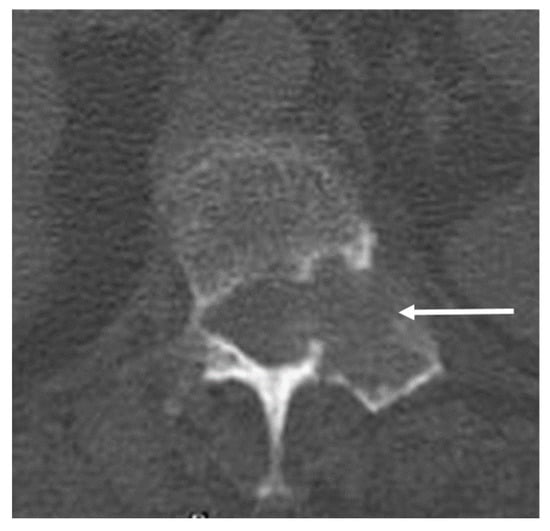

3.9. Aneurysmal Bone Cyst

| Aneurysmal bone cyst | Expansile lytic lesion with internal bone septations. | Fluid—fluid levels within the cysts, high T1 signal within layering fluid content due to haemorrhage. |